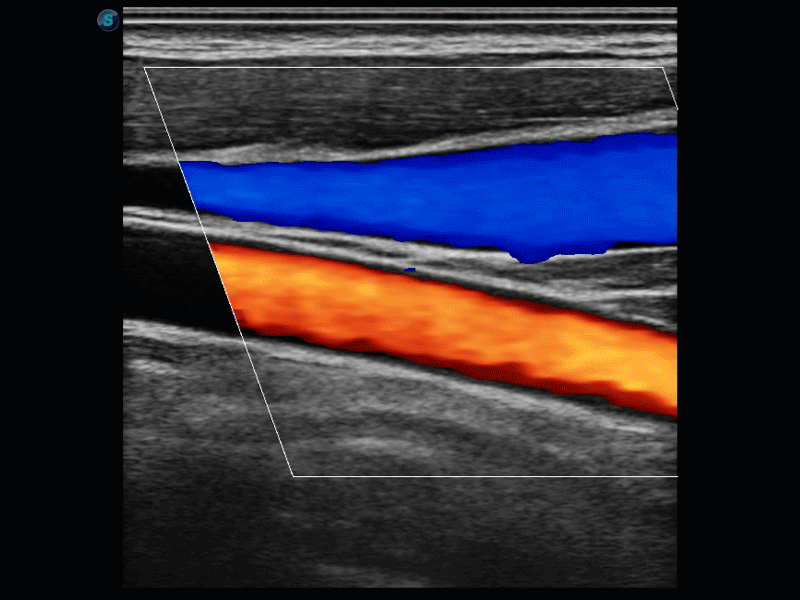

開立醫(yī)療通過不斷的技術(shù)創(chuàng)新,為大眾的生命健康提供持續(xù)關(guān)愛。P12 Plus采用全新一代超聲成像平臺,新平臺旨在將真實還原組織解剖結(jié)構(gòu)作為首要目標(biāo)。平臺采用全新集成化硬件模塊,搭載新一代芯片,系統(tǒng)性能得到大幅提升,為您的診斷提供了豐富的臨床信息。優(yōu)異的圖像表現(xiàn),豐富的探頭配置,全面的應(yīng)用功能,為您日常診斷提供了可靠的助手。

P12 Plus

彩色多普勒超聲診斷系統(tǒng)